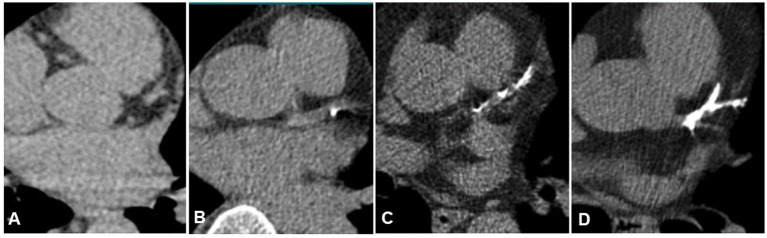

Background: A connection between cerebral white matter hyperintensities and coronary artery disease is widely discussed. Both conditions are more prevalent in the elderly. While white matter hyperintensities are often associated with small vessel disease, atherosclerosis is the primary cause of coronary artery disease.

Methods: We evaluated staging CT scans of the body and staging brain MRIs from patients with newly diagnosed malignant melanoma (without metastasis) between 01/01/2015 and 06/30/2023. CT scans were assessed for coronary artery disease using a modified overall visual assessment. Fazekas scores were used to evaluate the MRI for white matter changes. Additional clinical data were obtained from digital patient records.

Results: We analyzed data from 120 patients (57 females, mean age 68 years, standard deviation 14 years) and found a correlation between coronary artery disease and both age (r = 0.48, α = 0.04) and Fazekas score (periventricular r = 0.46, subcortical and deep white matter r = 0.55). A linear model including age, coronary artery disease, diabetes and arterial hypertension served as a predictor for white matter disease and showed significant correlations. Adding (1) atherosclerosis as well as (2) carotid stenosis to the model resulted in (1) a slight decrease in significance and (2) the unmasking of a potential spurious correlation with carotid stenosis.

Conclusion: There is a significant correlation between white matter hyperintensities and both carotid stenoses and coronary artery disease. This finding is clinically relevant: in patients with white matter hyperintensities and coronary artery disease, carotid stenosis should be ruled out.